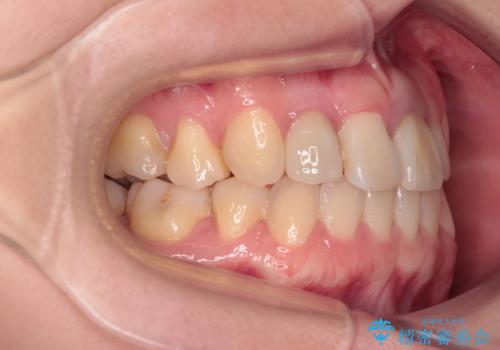

- 奥歯が痛いとのことで来院された患者様です。

上顎親知らず周辺の炎症と、神経組織の失活した歯の炎症による痛みが認められたため、親知らずの抜歯と根管治療を行いました。

根管治療を行った歯はクラウンによる補綴治療が必要となりますが、高校生の頃に行った矯正治療の後戻りも気になるとのことで、補綴治療を行う前に矯正治療を行うこととしました。

後戻りは軽度であり、インビザラインにて歯列を整え、その後にオールセラミッククラウンにて補綴治療を行うこととしました。